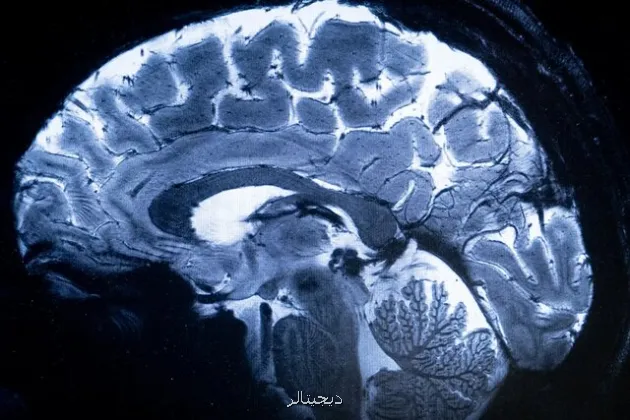

به گزارش دیجیتالر به نقل از ایسنا، چهاردهمین کنگره علوم اعصاب پایه و بالینی به منظور توسعه فعالیتهای پژوهشی، تبادل آخرین دستاوردها و یافته های تحقیقاتی و نیز گسترش تعامل و همکاری میان محققان، متخصصان و محققان با حمایت ستاد توسعه علوم و فناوری های شناختی از ۱۹ تا ۲۱ آذرماه در محل مرکز همایش های بین المللی رازی دانشگاه علوم پزشکی ایران برگزار می گردد.

این کنگره با تمرکز بر "پزشکی شخصی سازی شده"، فرصت مناسبی را برای محققان، پزشکان، دانشجویان و متخصصان فعال در زمینه علوم اعصاب پایه و بالینی فراهم می سازد تا در محیطی پویا به بحث و تبادل نظر، انتقال تجربه و اندیشه ورزی بپردازند و از این رهگذر پیوند بین تحقیقات علوم پایه و کاربردهای بالینی را در فضایی بین رشته ای تقویت نمایند.